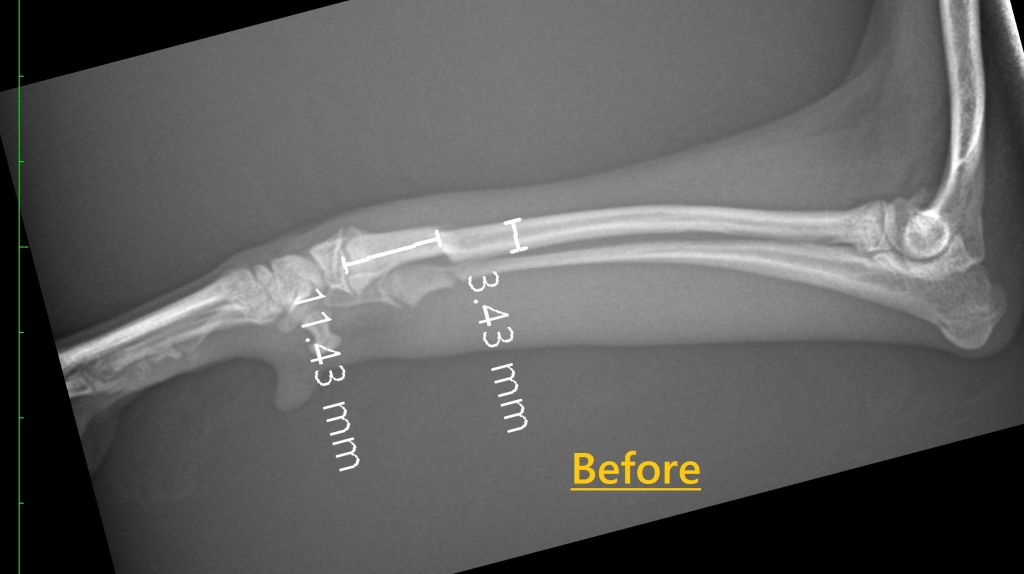

超小型犬(トイプードル)の前足骨折

体重1.3kgのトイプードルさん。

前肢の骨折で来院されました。

超小型犬の前肢は骨が非常に細く、固定方法の選択が重要になります。

今回はチタン製プレート(1.0mmスクリュー)を用いて整復固定を行いました。